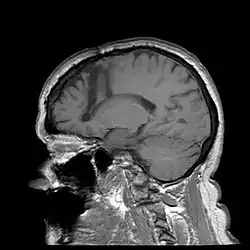

Lobotomy

One of the most notable treatments for the brain occurring in the 20th century was the lobotomy, which was invented in 1935 by Portuguese Neurologist Egas Moniz.[28] The lobotomy was a surgical procedure performed on the brain that targeted the frontal lobe, which is the part of the human brain that controls emotional response. The reason the lobotomy targeted this particular lobe was to reduce stress and other negative emotions to cure disabilities.[29]

Additionally, advancements in neurosurgery have enabled the treatment of certain neurological conditions associated with disabilities. Deep brain stimulation (DBS), for instance, has been increasingly used to manage symptoms of movement disorders like Parkinson's disease and dystonia. By implanting electrodes deep into specific brain regions and delivering controlled electrical impulses, DBS can help regulate abnormal neural activity, thereby improving motor function and reducing disability-related impairments.[45]